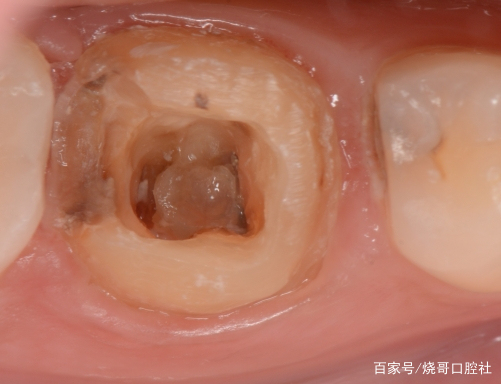

1、口腔鏡檢查:通過(guò)口腔鏡檢查,可以清晰地觀察到牙齒表面的牙洞以及牙洞內(nèi)的情況,醫(yī)生可以判斷牙洞是否已深入牙髓,并評(píng)估病情嚴(yán)重程度。

2、探診檢查:使用牙科探針檢查牙洞周圍組織的健康狀況,了解牙洞深度及與牙髓的關(guān)系。